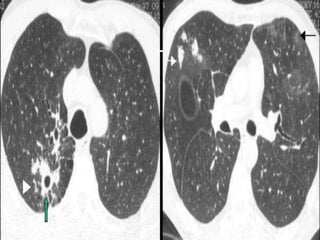

   Los hallazgos más frecuentes en la

tuberculosis primaria son las adenopatías y

las condensaciones

   La postprimaria las consolidaciones, los

nódulos y las cavidades, predominantes en

los segmentos apicales y posteriores de los

lóbulos superiores

   En algunos casos, sin embargo, es muy difícil

valorar si las lesiones radiológicas son activas

o no, especialmente si no se dispone de

estudios previos para comparar evolución

   En estos casos la TC y la TC de alta resolución

de tórax